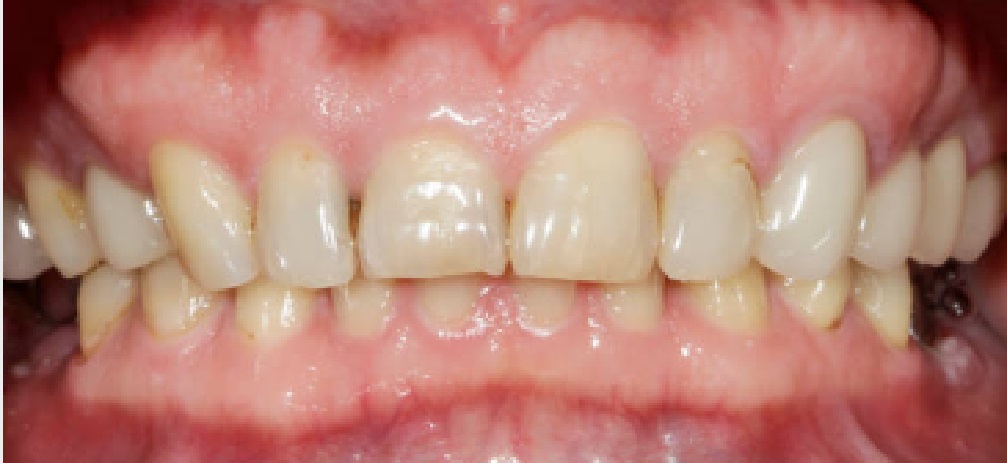

Проблема

Пациент обратился с жалобами на эстетическую неудовлетворенность передней группой зубов. Были изготовлены и установлены виниры E-MAX на передних зубах верхней и нижней челюсти.

Решение

Проделана следующая работа: установка керамических виниров повышенной эстетики E-MAX на передних зубах верхней и нижней челюсти.